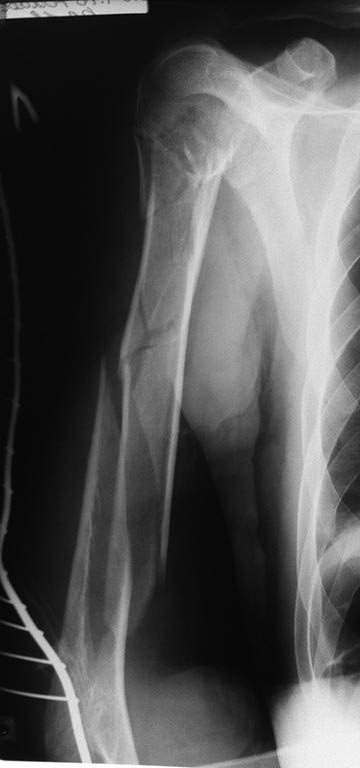

Пациент - пожилой мужчина, 61 года, с закрытым оскольчатым переломом

плечевой кости на всех уровнях (снимок прилагается). Травма в результате

ДТП от 23.04.16г. Монотравма.

оценки перелома головки плеча, КТ пока не доступна. Но наверняка перелом

головки плеча больше чем 2х-фрагментарный. Если оперировать, то

пластиной думаю слишком травматично. Если штифтовать, то не знаю

получится ли прихватиться 2 винтами в дистальном отломке (одного мне

кажется не достаточно). Да и в проксимальном не все так просто. Или все

таки оставить в покое все эти мысли об операции, и попытаться лечить по

Сармиенто? Но и здесь, как говорится: "консервативное лечение - это тоже